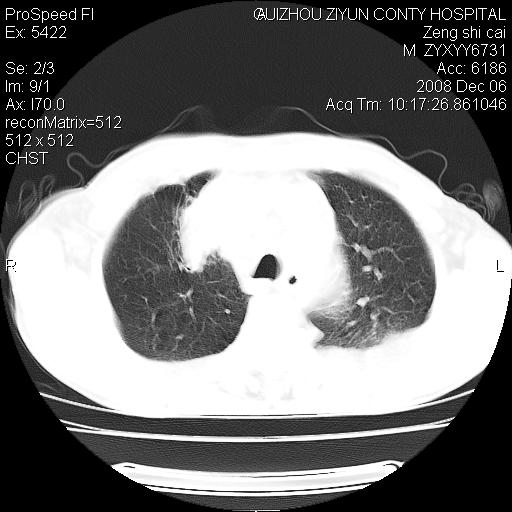

标题: CT16961:M、71岁,咳嗽半年,无血痰;胸片示右肺占位。 [打印本页]

标题: CT16961:M、71岁,咳嗽半年,无血痰;胸片示右肺占位。

右肺癌并纵隔淋巴结及胸膜转移可能性大

右肺癌并纵隔淋巴结及胸膜转移。建议气管镜

右肺纵隔型肺癌伴纵隔淋巴结及胸膜转移!

右肺纵隔型肺癌伴纵隔淋巴结转移!双侧胸水!

1)考虑右肺上叶纵隔型肺癌伴纵隔淋巴结转移。2)心包积液,双侧胸腔积液。

右肺癌并纵隔淋巴转移,腹膜后转移可能性大,两侧胸腔积液

右肺上叶纵隔型肺癌伴纵隔淋巴结转移。心包积液,双侧胸腔积液。

右上肺癌并纵隔淋巴结及胸膜转移。

右肺纵隔型肺癌伴纵隔淋巴结转移!双侧胸水\\心包积液

建议强化!主要鉴别是淋巴瘤与肺癌淋巴结转移。

右肺纵隔型肺癌伴纵隔淋巴结及胸膜转移